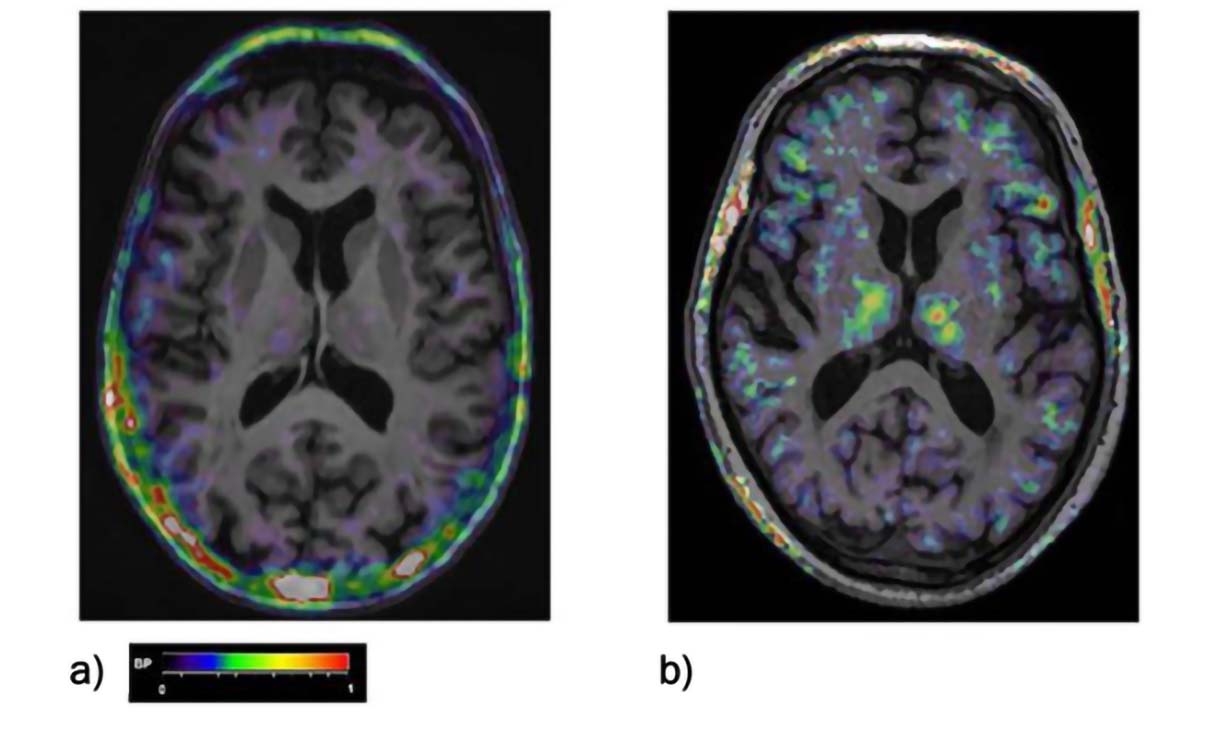

[11C](R)-PK-11195 PET BP maps co-registered to the individual MRI scan of a) a healthy control, b) of a MCI patient. BP increases can be seen fronto-temporal areas as well as in the thalamus. The color bar denotes BP values from 0 to 1